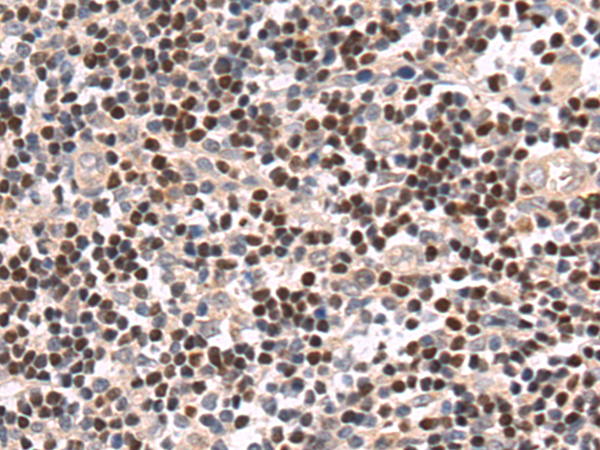

分类: 科研抗体货号: P07389别名: MUM1; LSIRF; SHEP8; NF-EM5应用: IHC反应种属: Human, Mouse